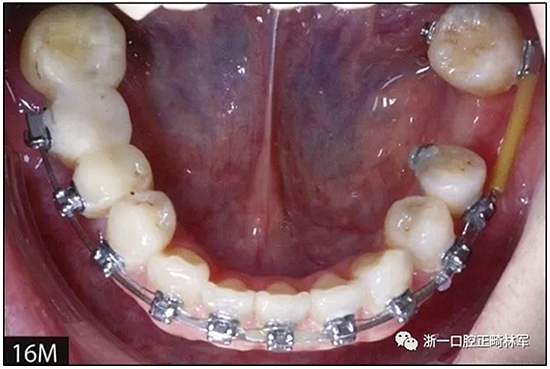

完全固定的Damon Q設(shè)備(加利福尼亞州Glendora的Ormco)與制造商指定的弓絲和附件一起使用。下頜弓,一開(kāi)始放入0.014英寸的鎳鈦弓絲,5個(gè)月后放入0.014×0.025英寸的鎳鈦弓絲。舌側(cè)扣和鏈圈放置在下頜尖牙和第二前磨牙上以控制扭轉(zhuǎn)。在治療的第7個(gè)月,將下頜弓絲換成0.017× 0.025英寸的β鈦絲。另一個(gè)舌側(cè)扣和鏈圈放置在下頜左側(cè)第三磨牙上以提供近中牽引力(圖9)。在16個(gè)月的治療結(jié)束時(shí),所有的扭轉(zhuǎn)都得到了矯正,缺牙間隙縮小到8 mm(圖8),但由于頰側(cè)骨板的嚴(yán)重吸收,牙槽嵴的寬度仍然很窄(約3 mm)(圖9)。通過(guò)正畸移動(dòng)下頜左側(cè)第二前磨牙,在前磨牙之間產(chǎn)生一個(gè)種植部位。在第一和第二前磨牙之間的弓絲上放置一個(gè)推簧,并將舌側(cè)扣和鏈圈放置在第一前磨牙和第三磨牙之間(圖9),在頰側(cè)和舌側(cè)施加力。施力均為輕力,每個(gè)表面上約2盎司(28.3 cN)以控制牙根側(cè)面的吸收。

圖9